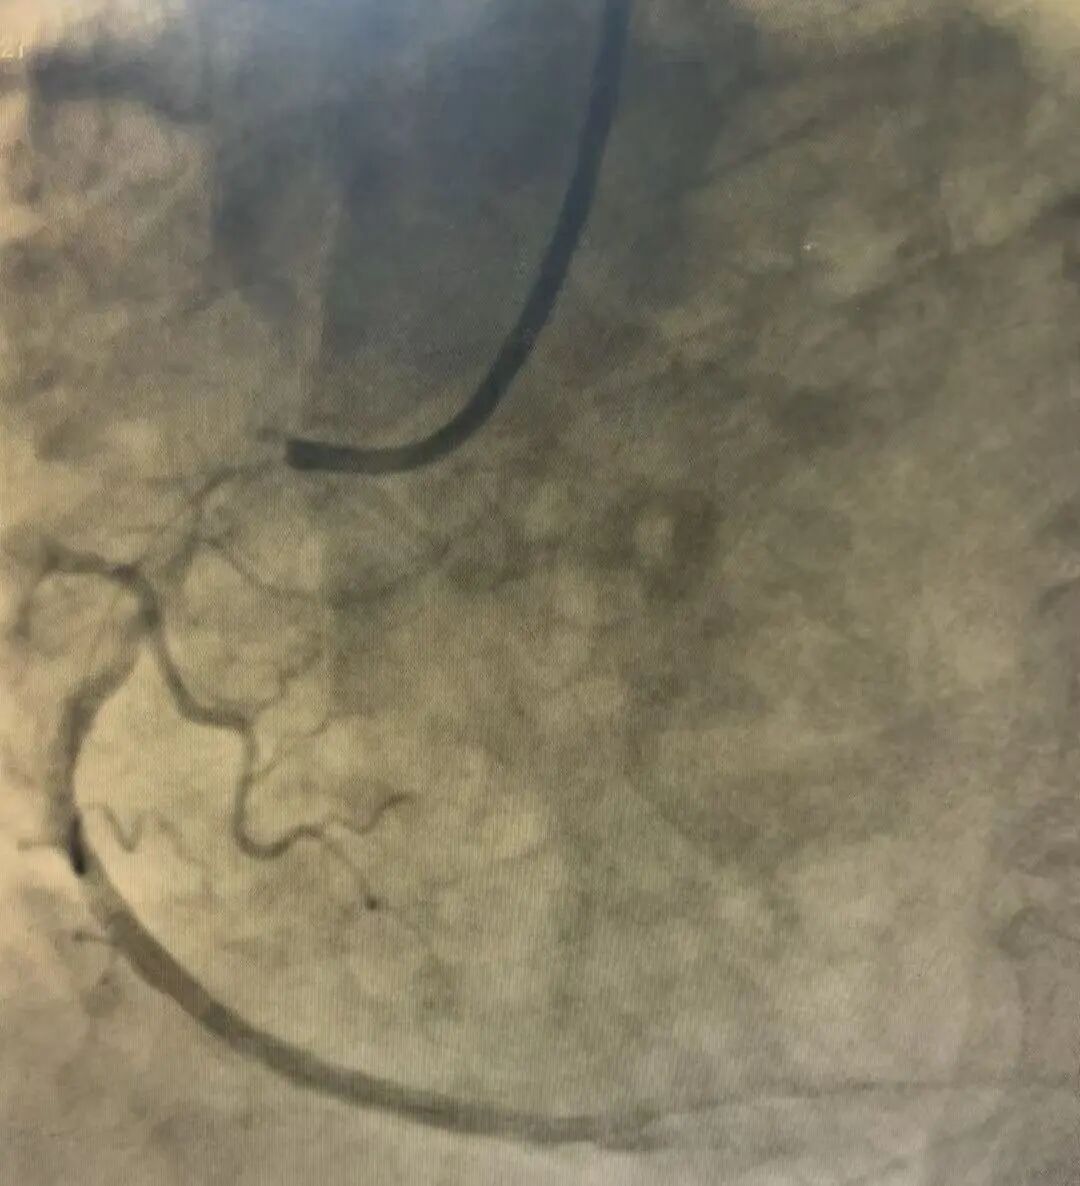

20时10分,由赵永富主任领衔的介入团队为患者施行急诊冠脉介入治疗。术中造影显示,患者心脏血管病变严重:前降支近端狭窄70%,右冠近端狭窄70%,而右冠远端更是达到了90%的严重狭窄,并可见血栓。情况危急!医疗团队精准操作,迅速在堵塞最严重的右冠病变处成功植入一枚支架,瞬间血流恢复,濒临坏死的心肌重获生机,患者的“生命通道”被成功重启!

术前造影

术后造影